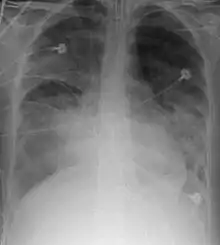

Chest X-ray is the most common method used for diagnosis,[37] and may be used to confirm a diagnosis already made using clinical signs.[20] Consolidated areas appear white on an X-ray film.[42] Contusion is not typically restricted by the anatomical boundaries of the lobes or segments of the lung.[27][43][44] The X-ray appearance of pulmonary contusion is similar to that of aspiration,[32] and the presence of hemothorax or pneumothorax may obscure the contusion on a radiograph.[25] Signs of contusion that progress after 48 hours post-injury are likely to be actually due to aspiration, pneumonia, or ARDS.[10]

Although chest radiography is an important part of the diagnosis, it is often not sensitive enough to detect the condition early after the injury.[35] In a third of cases, pulmonary contusion is not visible on the first chest radiograph performed.[7] It takes an average of six hours for the characteristic white regions to show up on a chest X-ray, and the contusion may not become apparent for 48 hours.[7][27][43] When a pulmonary contusion is apparent in an X-ray, it suggests that the trauma to the chest was severe and that a CT scan might reveal other injuries that were missed with X-ray.[2]